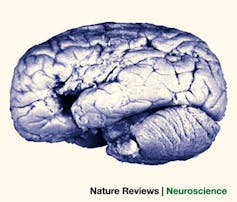

Vista lateral del cerebro del paciente

Rordern & Karnath, 2004.